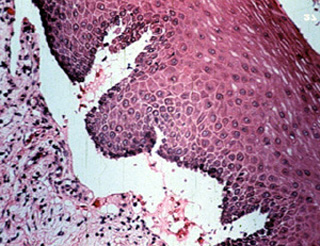

Estas vesículas y ampollas permanecen intactas en la cavidad oral porque la separación ocurre por debajo de la basal epitelial. No hay acantólisis de las células  epiteliales, y la vesícula es, por consiguiente, menos frágil. En esta microfotografía  puede verse al epitelio intacto techando la vesícula. Dentro del lumen hay proteínas y células inflamatorias.

A una mayor resolución, el epitelio puede verse entero, incluso la membrana basal. El tejido conjuntivo queda desnudo y hay una reacción inflamatoria mixta.